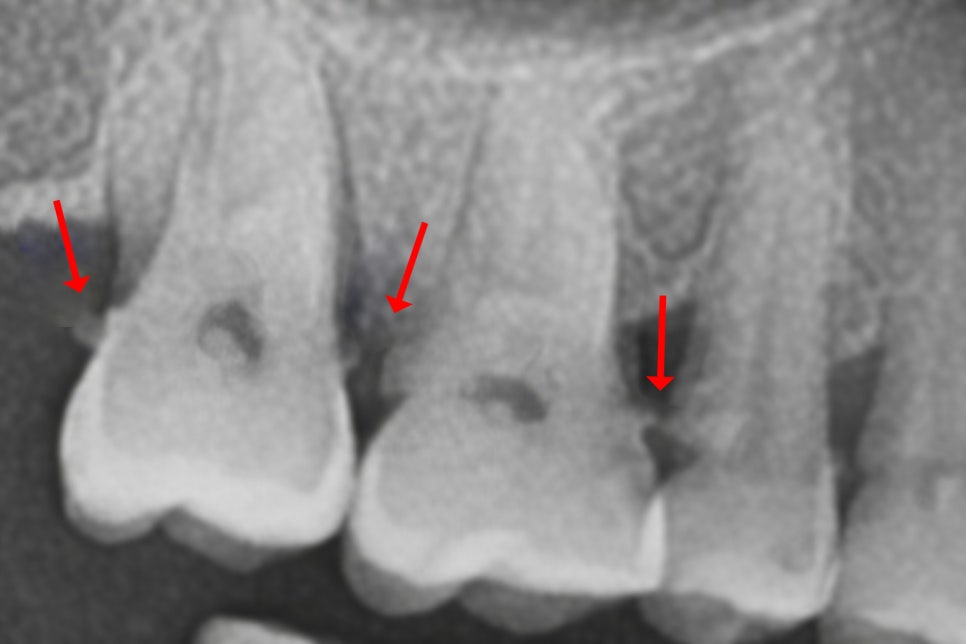

이미 침착물이 상당량

축적된 경우에는 오염된 치근 표면을

매끄럽게 다듬는 치근활택술이

필요한 경우도 있습니다.